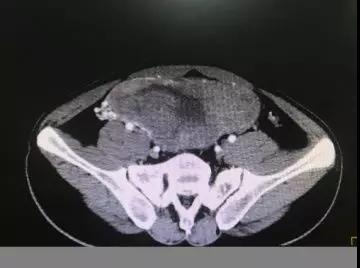

近日,有位39岁的男性患者,因腹痛、腹部隆起似“怀孕”来院就诊,经检查发现患者腹腔内有一巨大肿瘤,肿瘤血供丰富,而且有多根“引线”(动脉、静脉),同时肿瘤紧贴腹腔大血管,随时有破裂出血等可能,所以我们称它为“炸弹”。邱振雄决定尽快为患者排除“炸弹”。经术前详细评估及病情分析,该患者术前肿瘤来源部位不明,性质不明,术中肿瘤一旦破裂手术后肿瘤种植和转移的风险急剧增加;另外如果周围大血管破裂,随时有生命危险,这就要求我们术中需谨慎又谨慎,仔细再仔细。

术中见肿瘤非常巨大,20X15X10CM,占据整个盆腔,血供十分丰富,与周围大血管关系密切,一旦发生大血管破裂,患者随时有生命危险。胆大心细的邱振雄应用他娴熟手术技能、精准的解剖知识,经过2个多小时的耐心操作,完整的将“炸弹”拆除。目前患者恢复顺利,不日即可出院。